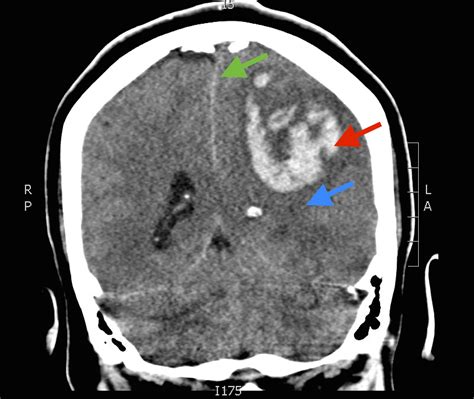

A brain bleed, medically referred to as a hemorrhagic stroke or intracranial hemorrhage, is a life-threatening medical emergency that requires immediate intervention. When a blood vessel within the brain ruptures, it creates pressure on delicate neural tissue, potentially leading to permanent damage or death. In many cases, brain bleed surgery is the only way to relieve this life-threatening intracranial pressure and prevent further complications. Understanding the nature of this procedure, the recovery process, and why it is performed is essential for patients and their families navigating this difficult medical journey.

The primary goal of brain bleed surgery is to stop the bleeding, remove the blood clot (hematoma) that is pressing against the brain, and alleviate the increased pressure inside the skull. When blood accumulates, the brain has no room to expand, leading to ischemia (lack of oxygen) and cell death. Surgeons must act quickly to restore normal blood flow and prevent secondary brain injury.